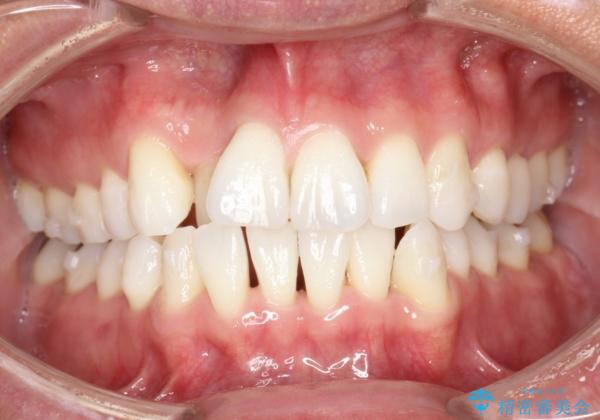

右上の前から2番目の歯が引っ込んで、下の前歯にはガタガタがありました。

上下の歯と歯の間を少量ずつ削りスペースを作り、インビザラインにて並べる計画としました。

目立たずに矯正治療を終えることができたことに満足していただけました。